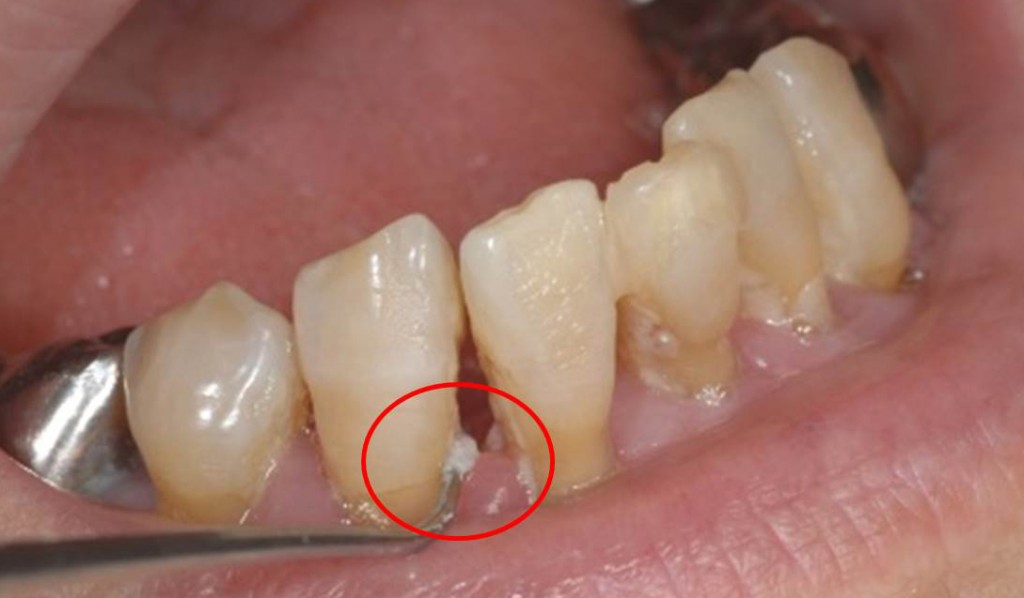

下写真は、いわゆるプラークです。これは食べカスではありません。約7割が細菌、その他は細菌の代謝物になります。時間が経つと歯の表面がザラザラしてくるのは、細菌が繁殖しているからなのです。